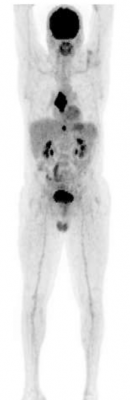

In a paper published in the New England Journal of Medicine, the scientists show that a positron-emission tomography (PET) scan immediately after treatment with chemotherapy can identify patients who have a very good outcome without additional radiotherapy.

The 602 patients who agreed to take part in the ‘RAPID’ trial had a PET scan performed after their chemotherapy. Patients who tested positive received radiotherapy. Those who tested negative were divided into two groups – one group of 211 patients received no further treatment, while the other group of 209 had the standard radiotherapy.